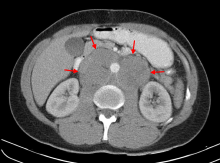

Retroperitoneal lymphadenopathies of testicular seminoma, embrace the aorta. Computed tomography image.